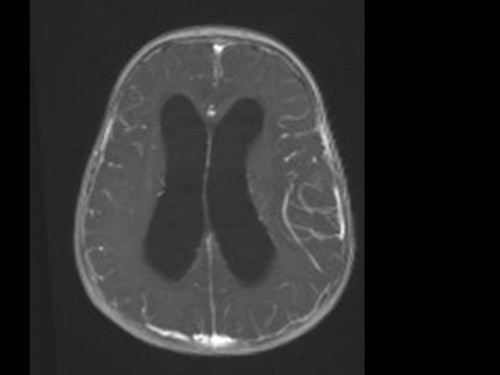

10 Monate altes Mädchen. Der Kinderarzt stellt fest, dass das kleine Mädchen einen recht großen Kopfumfang hat, nicht mit den Augen fixiert und anscheinend auch nicht richtig sehen kann. Damit bestätigt er die größten Befürchtungen der Eltern, denen in den letzten Wochen aufgefallen war, dass ihre Tochter nach keinem Spielzeug mehr greift und sie nur dann anlächelt, wenn sie zu ihr sprechen.

Bildgebung - MRT